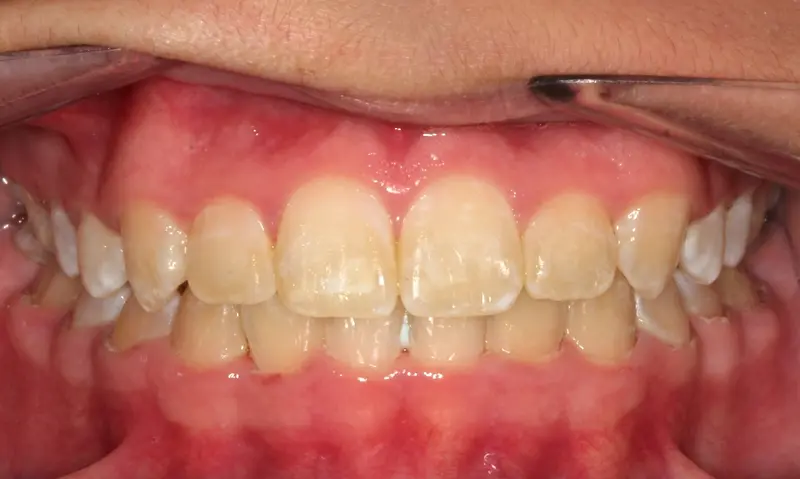

Skeletal Correction 22 Months

The Extraction Myth

The Diagnosis

Bimaxillary protrusion (teeth flaring forward) causing lip incompetence. The patient struggled to close his lips comfortably, straining the chin muscle (mentalis).

The Engineering

A strategic extraction plan (4 premolars) allowed us to retract the front teeth. Note the dramatic improvement in chin projection and facial balance. The extractions did not flatten the face; they harmonized it.

Instrument: Intelligent Brackets

After treatment: The Extraction Myth

After

Before treatment: The Extraction Myth

Before